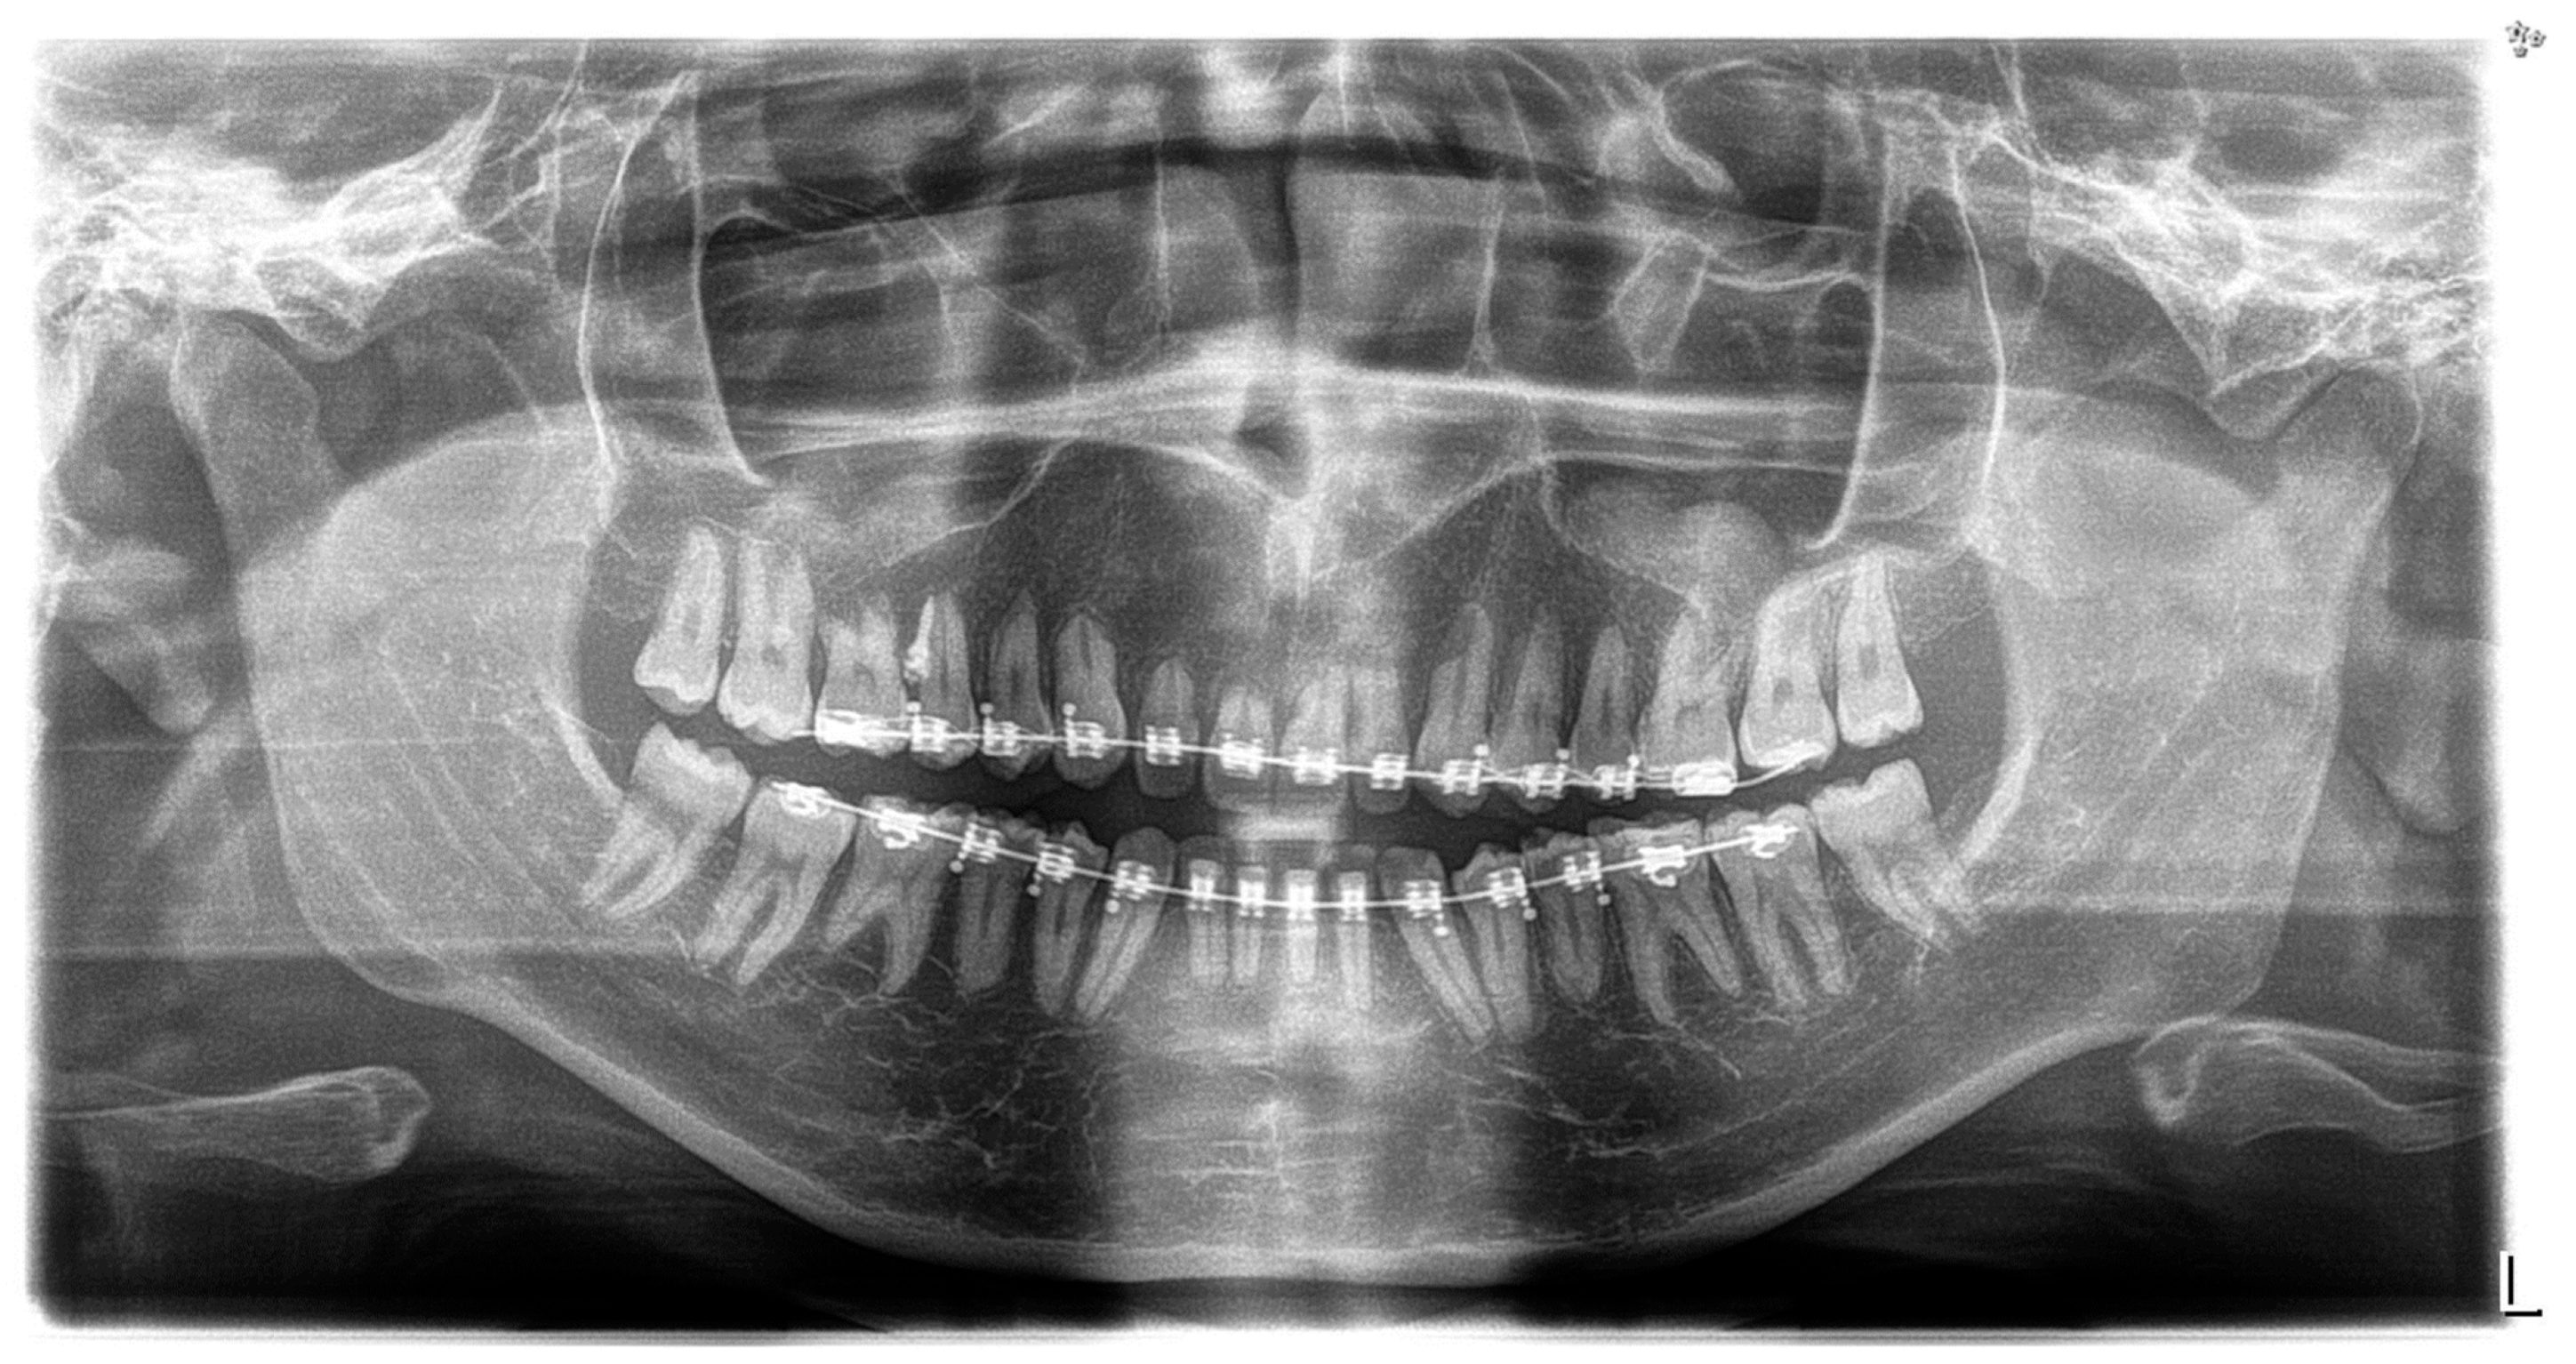

3. Results

2.3. Treatment Progress